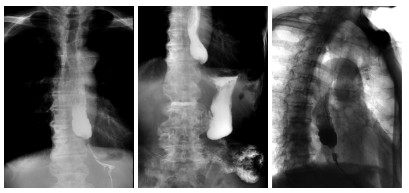

Construction of risk model of esophageal and gastric varices rebleeding in cirrhosis based on 2D-SWE

GUO Li, LOU Junge, YAN Yuanyuan

2025, 23(12): 2042-2045. doi: 10.16766/j.cnki.issn.1674-4152.004287

83 4

Abstract:

Objective  The pathophysiological mechanism of esophageal and gastric varices (EGV) rebleeding in liver cirrhosis is complex, and the mortality rate is high. Identifying the literature factors of EGV rebleeding is important to reduce the mortality rate. Two-dimensional shear wave elastography (2D-SWE) can evaluate the degree of liver hardness and pathological changes in a non-invasive and quantitative manner. This study discusses the construction of the EGV rebleeding risk model based on 2D-SWE to provide a reference for clinical prevention and treatment.  Methods  A total of 162 patients with EGV with cirrhosis admitted to Zhengzhou Central Hospital Affiliated to Zhengzhou University from January 2020 to December 2022 were selected. According to whether rebleeding occurred, the patients were divided into the no rebleeding group (127 cases) and the rebleeding group (35 cases). The risk factors of EGV rebleeding in patients with cirrhosis were analyzed by Logistic regression. To construct a nomogram prediction model for the EGV rebleeding in cirrhotic patients, and evaluate the prediction efficiency of the nomogram model.  Results  The proportion of Child-pugh grade A liver function, the proportion of mild esophageal and gastric varices and the level of ALB in the group without rebleeding were higher than those in the group with rebleeding (P < 0.05), and the proportion of first ligation, liver hardness and spleen hardness in the group with no rebleeding were lower than those in the group with rebleeding (P < 0.05). Logistic multivariate results showed that Child-Pugh grade of liver function, liver hardness, spleen hardness, and ALB were independent influencing factors for EGV rebleeding in cirrhosis (P < 0.05). A nomogram model for predicting EGV rebleeding in cirrhosis was established according to the logistic multi-factor results, and the model was verified. ROC curve analysis results showed that the C-index of the nomogram model was 0.903 (95% CI: 0.846-0.975), and the measured value of the nomogram model was basically consistent with the predicted value, with high predictive value and good clinical effectiveness.  Conclusion  2D-SWE detection of liver and spleen hardness is a risk factor for EGV rebleeding, and the prediction model based on this nomogram has a good predictive effect on EGV rebleeding.